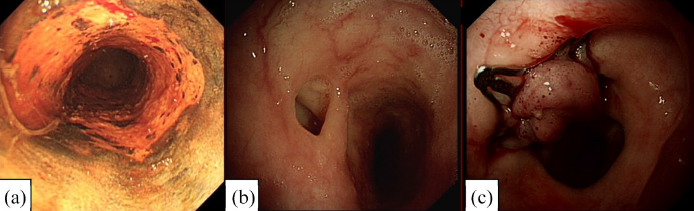

Prótesis:

- Existen prótesis metálicas autoexpandibles totalmente cubiertas, prótesis metálicas autoexpandibles parcialmente cubiertas y prótesis plásticas.

- Vienen de diferentes tamaños y diámetros y deben ser lo suficientemente largas para cubrir 3-5 centímetros proximal y distal al defecto.

- El procedimiento se realiza bajo fluoroscopia y visualización endoscópica. En 48-72 horas se coloca contraste para verificar que no existan fugas y comenzar la dieta oral.

- La complicación más frecuente es la migración de la prótesis.